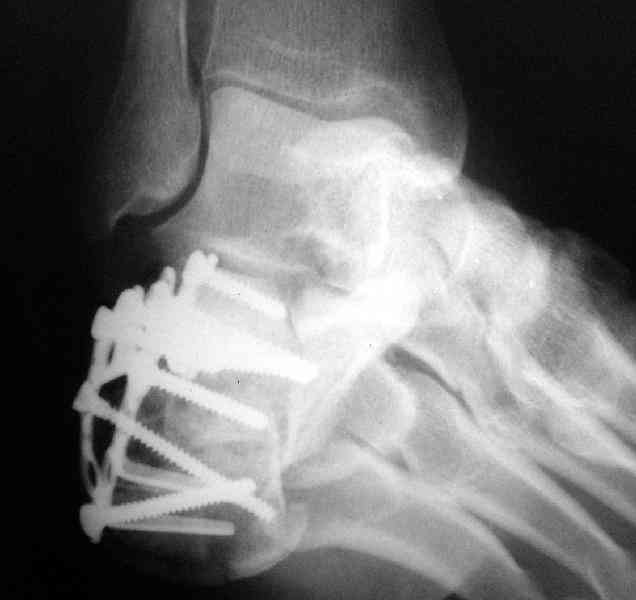

Пяточной пластиной

Открытый и закрытый способы лечения.

Its a comminuted one.

I would have a CT prior 2 surgery(If u have to postpone a surgery for it - I would operate without one)

I myself would reduce it with EX-FIX and depending on the result would consider a plate on the table.

MOST OF MY COLLEGUES WOULD OPEN IT LATERALLY( a flap) and having a proper reduction would put a plate.

Если нет опыта в остеосинтезе пяточной пластиной то лучше начать с экскохлеации полости кистозного образования и заполнения его остеоиндукторами Коллапан, Тутопласт, etc.Закрытая репозиция с рентгенконтролем на столе и перкутанная фиксация спицами пяточного бугра с фиксацией в эквинусе могут дать вполне приемлемый результат.

Вправление задней фасеты с восстановлением таранно-пяточного угла возможно минимально-инвазивным методом Essex-Lopresti - под ЭОП или графическим контролем введенной в пяточный бугор толстой спицей или стрежнем Штеймана, которые служат рычагом. Для удержания вводим несколько тонких спиц Киршнера, фиксация в эквинусе.Подробнее в Margo anterior 1-2 2000\издание АО Матис в России, на сайте www.mathys.ru в архиве есть все выпуски. Метод внедрен у нас с 2000 года и дает неплохие результаты.